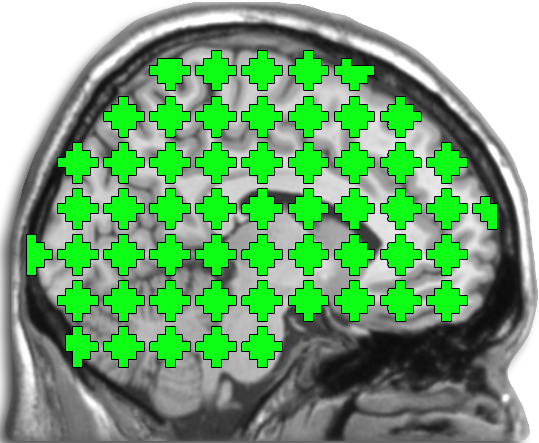

In this work, we produced a whole-brain resting state functional connectome as follows. First, non-overlapping spherical nodes are placed throughout the entire brain in a regularly-spaced grid pattern, with a spacing of mm; each of these nodes represents a pseudo-spherical ROI with a radius of mm, which encompasses voxels (the voxel size is mm). For a schematic representation of the parcellation scheme, see Fig. 1. Next, for each of these nodes, a single representative time-series is assigned by spatially averaging the BOLD signals falling within the ROI. Then, a cross-correlation matrix is generated by computing Pearson’s correlation coefficient between these representative time-series. Finally, a vector of length is obtained by extracting the lower-triangular portion of the cross-correlation matrix. This vector represents the whole-brain functional connectome, which serves as the feature vector for disease prediction.

The grid-based scheme for brain parcellation used in this work provides numerous advantages. Of note, this approach has been validated in previous studies [12, 34, 35]. Furthermore, the uniformly spaced grid is a good fit with our implementation of fused Lasso and GraphNet, as it provides a natural notion of nearest-neighbor and ordering among the coordinates of the connectome. This property also turns out to be critical for employing our optimization algorithm, which will be discussed in Sec. 2.3. This is in contrast to alternative approaches, such as methods that rely on anatomical [36, 11] or functional parcellation schemes [37]. Anatomical parcellations in particular have been shown to yield inferior performance to alternative schemes in the literature [38]. Additionally, grid-based approaches provide scalable density: there is a natural way to increase the spatial resolution of the grid when computational feasibility allows. In particular, to increase node density, one could reduce the inter-node distance and also reduce the node size such that suitable inter-node space remains. This scalable density property turns out to be quite important, as our grid-based scheme is considerably more dense than standard functional parcellations (e.g., [37, 39]) that use as many as several hundred fewer nodes, and thus have tens of thousands fewer connections in the connectome. Finally, the use of our grid-based scheme naturally leaves space between the nodes. While on the surface this may appear to yield incomplete coverage, this is in fact a desirable property to avoid inappropriate inter-node smoothing. This may result as a function of either the point-spread process of fMRI image acquisition or be introduced as a standard preprocessing step. In recognition of these advantages, we have elected to use a grid scheme composed of pseudo-spherical nodes spaced at regular intervals.

Grid-based Brain Parcellation Scheme with -nodes